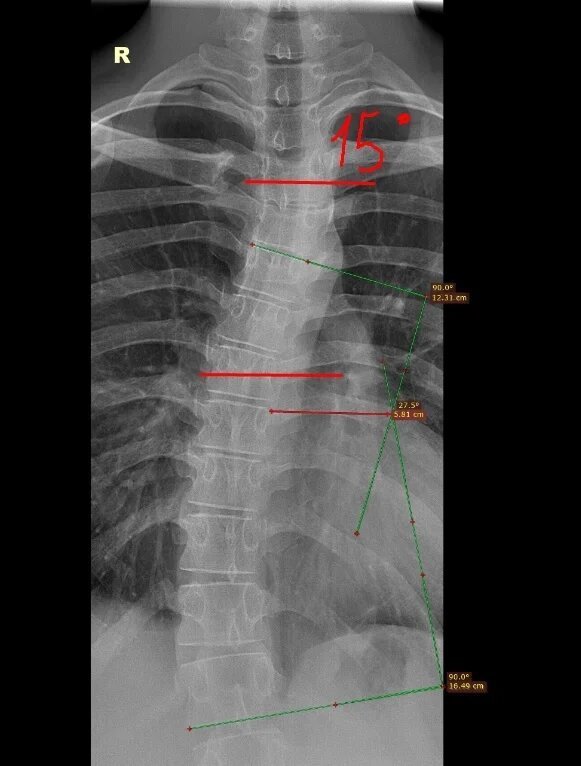

Ко мне обратился призывник с диагнозом: сколиоз грудного отдела позвоночника, он сделал снимки(самообращение) в своей пол-ке, где ему отдали на руки только описание, где фигурировала правосторонняя сколиотическая дуга с углом искривления 15 град-соответствует сколиозу 2 (второй) ст.- категория годности к военной службе по ст.66г- Б4(годен к в/сл с незначительными ограничениями). Переделав снимки в частной клинике в заключении у него был описан больший градус. Рентгенологические снимки с частных клиник военкомат не принимает. Расчертив снимки призывника у меня получились результаты: правосторонний сколиоз грудного отдела позвоночника 3(третьей) ст. по методу Кобба(27 градусов),3(третьей) ст. по Фергюсону(26 град),что соответствует ст. 66 в-В(ограниченно годен к военной службе).В дальнейшем призывник добился переснятия снимков по направлению от военкомата, при повторном расчерчивании-подтвердилась категория годности В(ограниченно годен к в/сл). Если вам требуется консультация по категор

Как были первоначально расчерчены снимки в пол-ке.